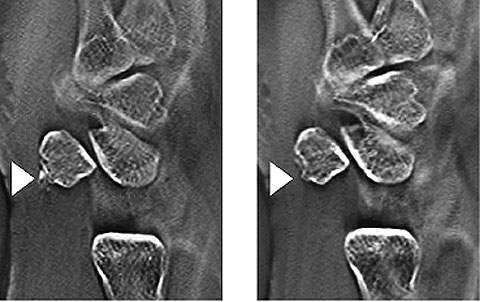

Case 3 – 58-year-old female: a patient who had fallen down stairs at home was immediately hospitalized after CT confirmed a Jefferson fracture. The treatment for a Jefferson fracture is determined according to whether the transverse ligament is intact or broken. This is evaluated from the degree of lateral dislocation of the lateral mass of the atlas with respect to the lateral mass of the axis on both sides³. Frontal tomosynthesis of the cervical vertebrae was performed the day after hospitalization. It provided better evaluation of the lateral mass of the atlas and axis than general radiographs or CT (Fig. 12). Conservative treatment by Halo vest fixation was performed.